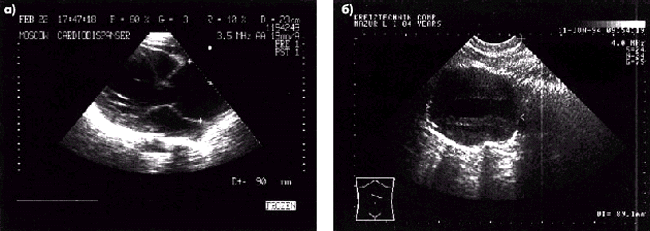

Аневризма сосудов.Диагноз аневризмы аорты ставят при локальном (ограниченном) выбухании стенки аорты или при диффузном увеличении диаметра грудной или брюшной аорты в 2 раза по сравнению с нормой (рис. 4.33). В области расширения, как правило, заметно снижается скорость кровотока; он становится неупорядоченным и даже разнонаправленным. Эти изменения обычно хорошо выявляются при ультразвуковой допплерографии.

Сходные изменения обнаруживают при аневризме крупных ветвей аорты, хотя при применении В-режима исследования часто возникает необходимость дифференцировать обнаруженное расширение сосуда с кистами и псевдокистами поджелудочной железы, почек и других органов, а также с наличием дивертикулов тонкой кишки и гидронефрозом. В этих случаях особенно показано использование ультразвуковой допплерографии, которая позволяет достаточно легко различать эти образования.

| Рис. 4.33. Двухмерные эхокардиограммы (а, б) при аневризме аорты |